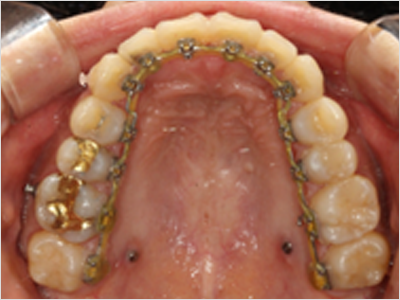

설측교정은 교정장치를 상악과 하악 모두 안쪽에 부착하는 반면,

콤비 교정은 상악은 안쪽,

하악은 바깥쪽에 부착

한다는 차이점이 있습니다.

설측교정

상악

교정장치를 안쪽에 부착

하악

콤비교정

교정장치를 바깥쪽에 부착

• STEP 02 설측 맞춤형 브라켓 지그 제작

교정전문의와 CAD/CAM전문가의 디자인으로

개별적인 설측 지그를 제작합니다.

• STEP 03 장치 부착 및 치료

IDBS(간접부착)방식을 이용하여

정밀한 위치에 장치를 부착합니다.